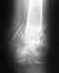

Был остеосинтез бедренной кости штифтом и наложенным проволочным серкляжным швом на соединение отломков. Все зажило, штифт извлекли. А вот проволоки оставили и сказали, что их не вынимают. По собственному желанию лег на операцию снять с кости проволоки. К сожалению удалось извлечь только 90% конструкции. Один фрагмент проволоки (примерно 5см длинной и 1мм в диаметре) в кости "запаялся", "прикипел"...так и не удалось вытащить...хирург со всей дури тащил, но тупо обкусывались концы и все тут Вообщем, нужно сделать на этой же ногу МРТ коленного сустава. Хирург сам не знает и отдал мне кусок проволоки и сказал понести с собой на МРТ и показать, спросить можно ли делать или нет. Я позвонил записывать на диагностику мрт и по телефону не сказали, что никто смотреть на проволоку не будет там и никто ничего не скажет...и что я сам должен знать что это такое и можно ли мне делать МРТ.Я конечно схожу и к хирургу еще раз и по МРТ центрам, но все же может кто знает и имел подобны опыт, даст ответ?!Вот снимки, один со штифтом и проволоками, а другой это когда уже все, что можно с ноги сняли (виден оставшийся фрагмент проволоки):http://itmages.ru/image/view/826917/98cffb09http://itmages.ru/image/view/826918/709795fe